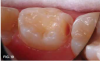

Case 1. A 9-year-old girl had a distal caries lesion of the primary canine tooth and mesial caries of the approximating primary first molar (Figure 1). With no local anesthesia and no discomfort reported by the child, a high-speed diamond bur was used to trim open the contact, exposing the lesions (Figure 2). After the site was air-dried, a flexible interdental pick was used to apply the SDF solution (Figure 3), which was blotted dry with a cotton swab after 60 seconds (Figure 4).

Fig 1. 9-year-old patient with proximal caries lesions of canine and  rst molar.

Fig 1

Fig 2. Surfaces trimmed; caries lesions exposed.

Fig 2

Fig 3. SDF applied with  exible proximal pick.

Fig 3

Fig 4. Caries lesion of canine, a few minutes after SDF applied.

Fig 4